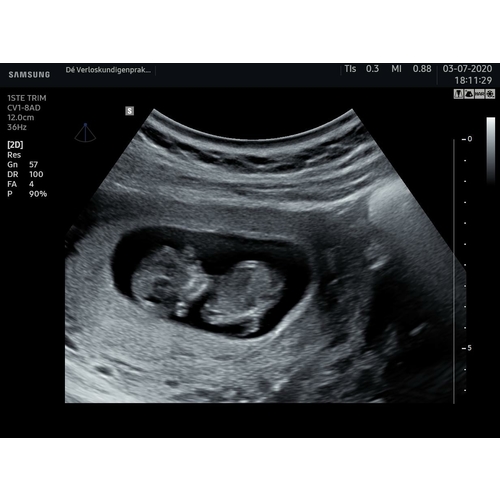

Heb het zelf ook hoor, als ik ga staren naar mijn echo fotos dan zie ik vanalles en maak ik mij helemaal gek😲

Heb je wel eens filmpjes gezien op youtube/internet waar ze je laten zien hoe de baby ontwikkeld bij welke week? Dan kan je zien dat rond het aantal weken dat jij nu bent de baby er helemaal niet uitziet als hoe ze worden geboren. Niks om je zorgen over te maken

Voor 3D is het vruchtje dan ook nog te klein... Het is amper een paar centimeter groot én in volle ontwikkeling. Helemaal niks raar aan de hoofdvorm, en allesbehalve een reden om je zorgen over te maken.